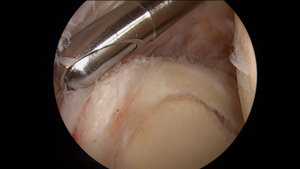

45yo male weightlifter with several months of anterior shoulder pain, unable to perform chest, shoulder, and arm exercises at gym for nearly 2 months. MRI revealed extensive biceps tendonitis and tearing. Patient failed nonsurgical treatment and elected for shoulder arthroscopy

Intraarticular biceps tendon at its attachment to superior glenoid labrum with extensive complex tearing; biceps tendon located at 12 o'clock on photo #2

Arthroscopic shaver device to debride biceps tendon and release to perform subpectoral biceps tenodesis procedure